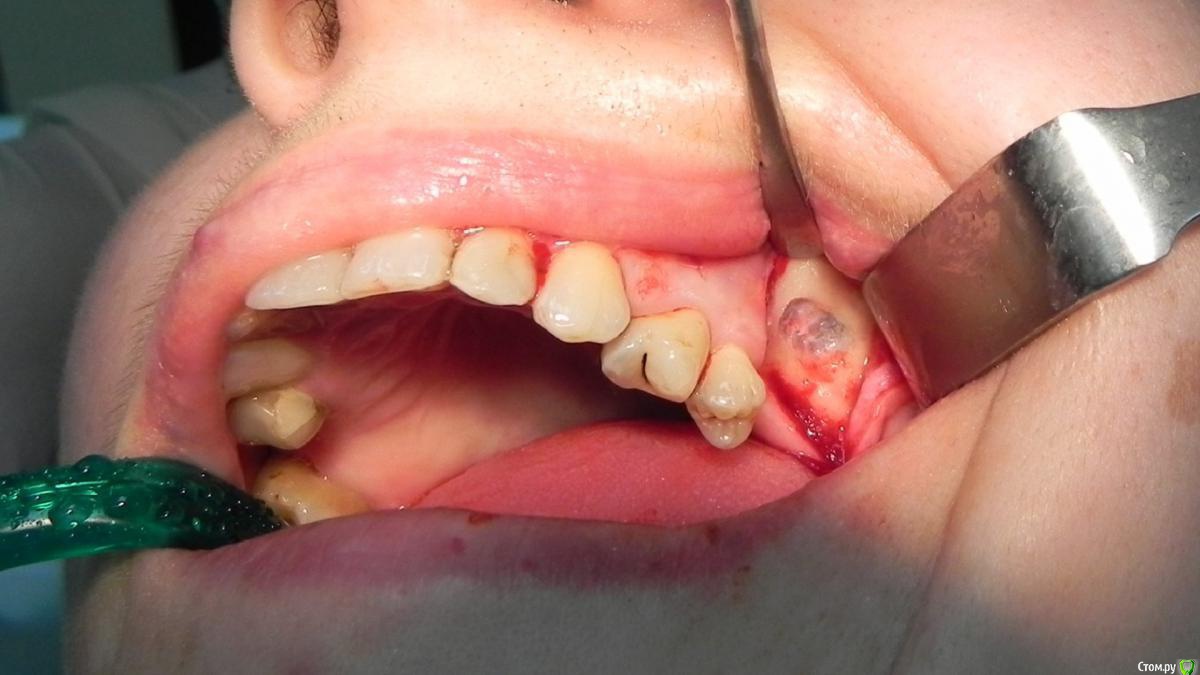

Kostoprav Опубликовано 7 августа, 2015 Поделиться Опубликовано 7 августа, 2015 доступпрепаровка шаровидной костной фрезойпри отслаивании мембраны образовалась маленькая перфа перфорацию" проклеил" коллагеновой мембранойпод мембрану внесен материалмембрана на окноготово может кому из начинающих этот пост полезен будет 1 Ссылка на комментарий

Jurai Опубликовано 7 августа, 2015 Поделиться Опубликовано 7 августа, 2015 Прикольные 4 и 5 у пациентки Ссылка на комментарий